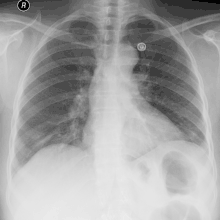

Эмпиема плевры

Эмпиема плевры (пиоторакс, гнойный плеврит) — скопление гноя в плевральной полости (разновидность плеврального выпота). Как правило, эмпиема плевры развивается в связи с инфекционным поражением лёгких (пневмонией) и часто ассоциирована с парапневмоническим выпотом. Различают три стадии эмпиемы: экссудативная, фибринозно-гнойная и организующая. При экссудативной фазе происходит накопление гноя. Фибринозно-гнойная стадия проявляется осумкованием плевральной жидкости с формированием гнойных карманов. В конечную, организующую стадию, происходит рубцевание плевральной полости, которое может привести к замуровыванию лёгкого[1].

Для хронической эмпиемы характерно формирование симптома барабанных палочек. Отмечается укорочение перкуторного звука и ослабление везикулярного дыхания с поражённой стороны. Для диагностики используется подсчёт лейкограммы, рентгенография и компьютерная томография грудной клетки, ультразвуковое исследование[1].